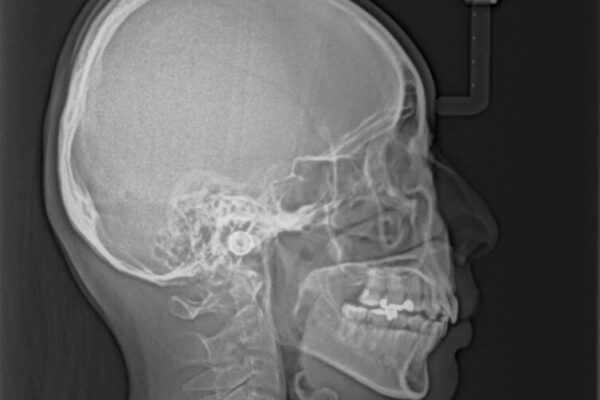

上の前歯の突出感を気にして来院された患者様です。

目立たない装置を希望とのことで、上顎左右第一小臼歯を抜歯し、インビザラインにて矯正治療を行うこととしました。

インビザラインにて抜歯矯正を行うと、高頻度で奥歯が咬み合わなくなります。

また、抜歯スペースに向けて奥歯が移動する際、必ず傾斜して移動するため、仕上がりの咬み合わせはワイヤー矯正と比べて明らかに劣ります。

抜歯スペースが閉じてからも咬みにくさ改善のためマウスピース矯正を継続するため、治療期間は長期化します。

治療前

• 上顎前歯の突出を軽減 インビザラインによる抜歯矯正 治療前画像